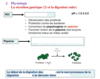

Que représente les fleches rouges et noires?